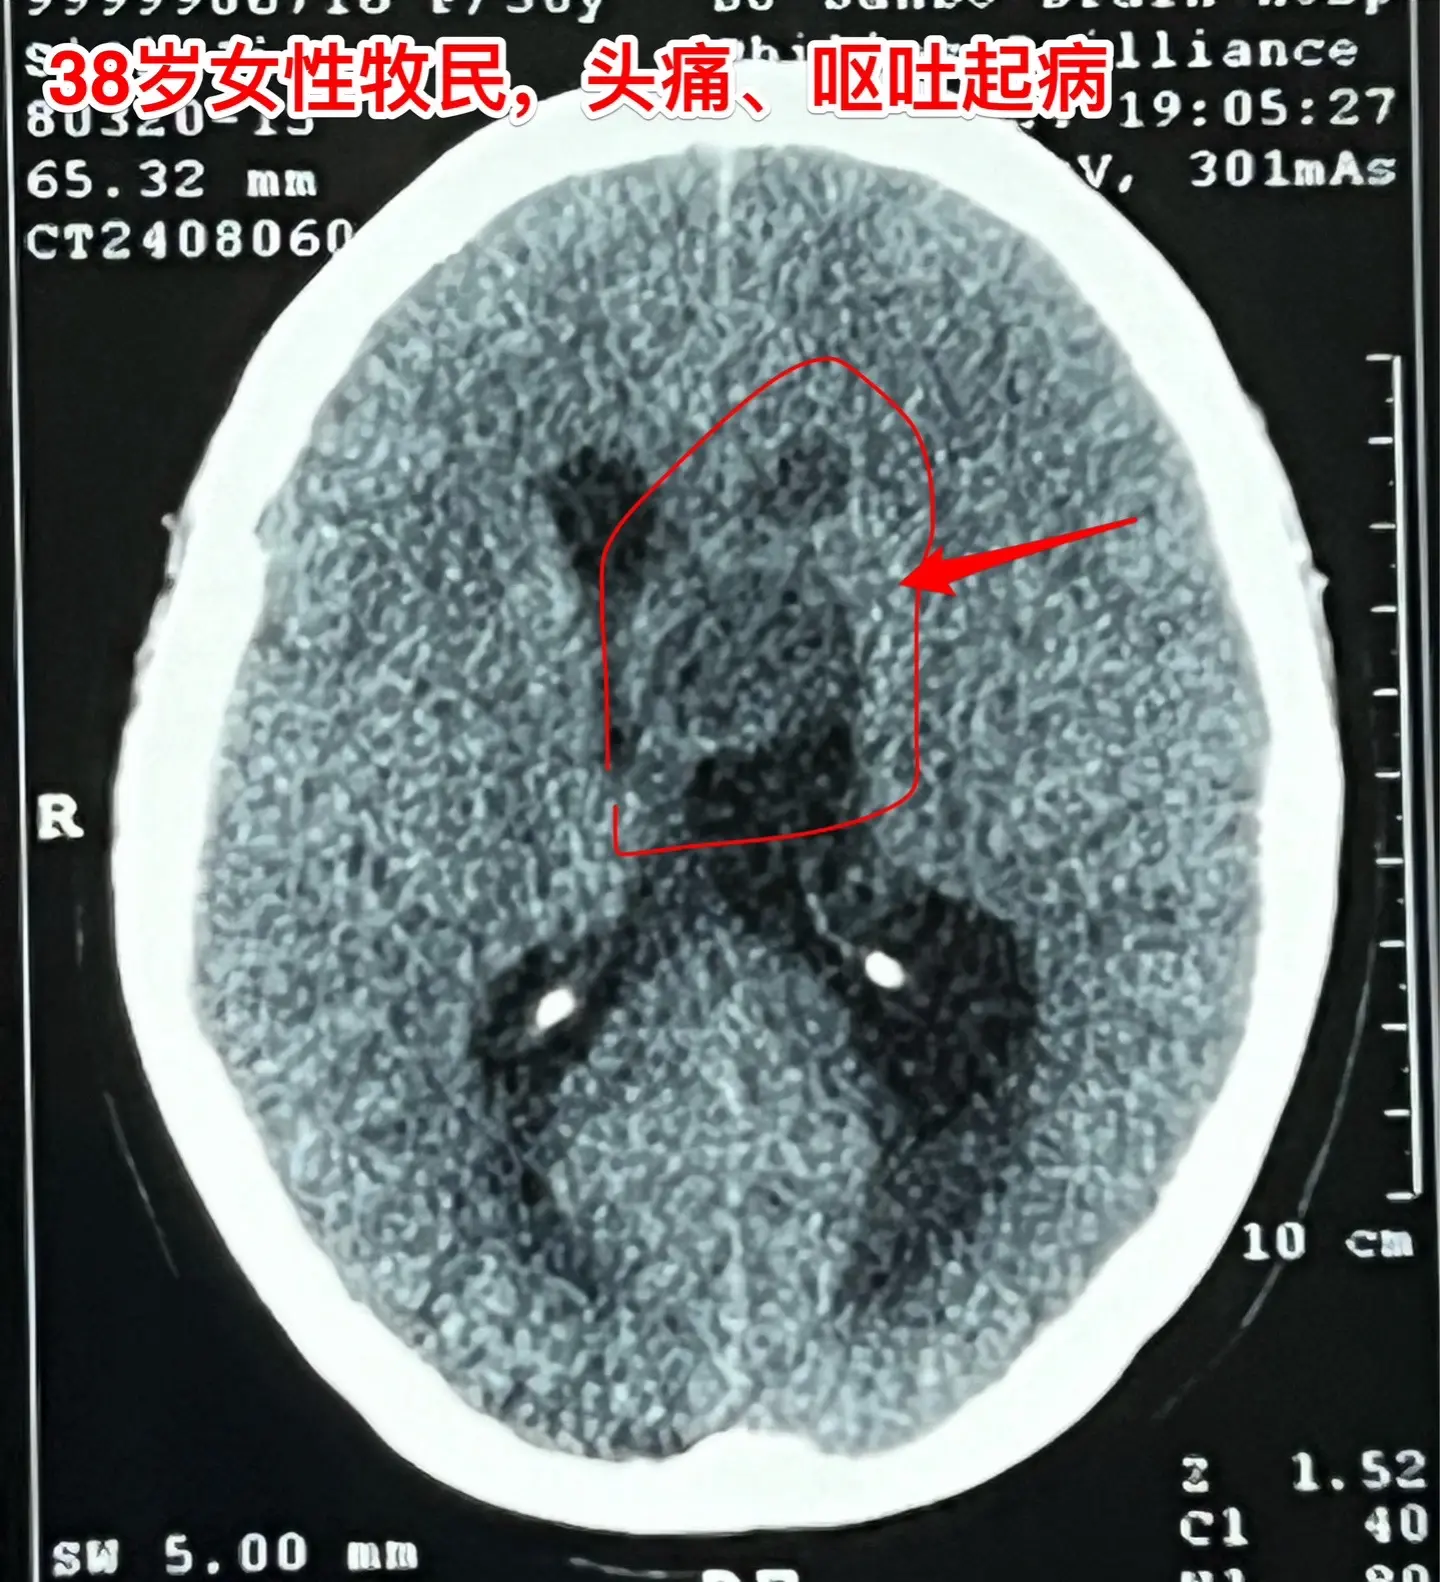

38岁女性脑部发现肿瘤、平时心跳很慢。38岁女性,西乌珠穆沁旗牧民,因...

2024-08-11 14:17